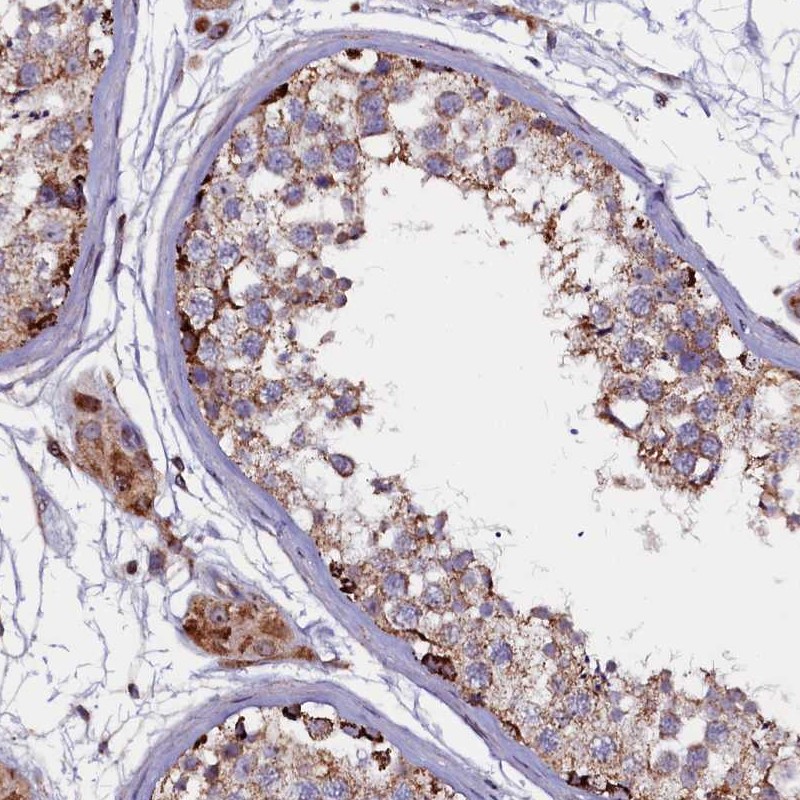

Immunohistochemical staining of human testis shows strong cytoplasmic positivity in cells in seminiferous ducts and Leydig cells.